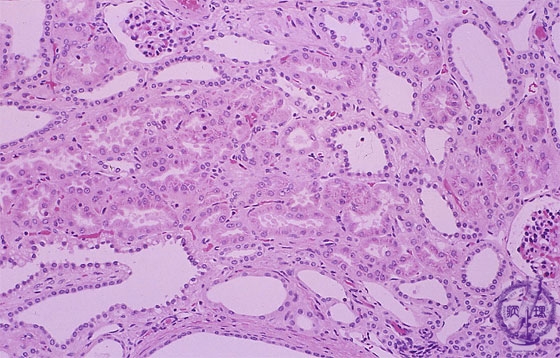

Microscopic view (H&E, low power, high power); All collecting tubules have irregular cylindrical dilation and cyst formation is observed